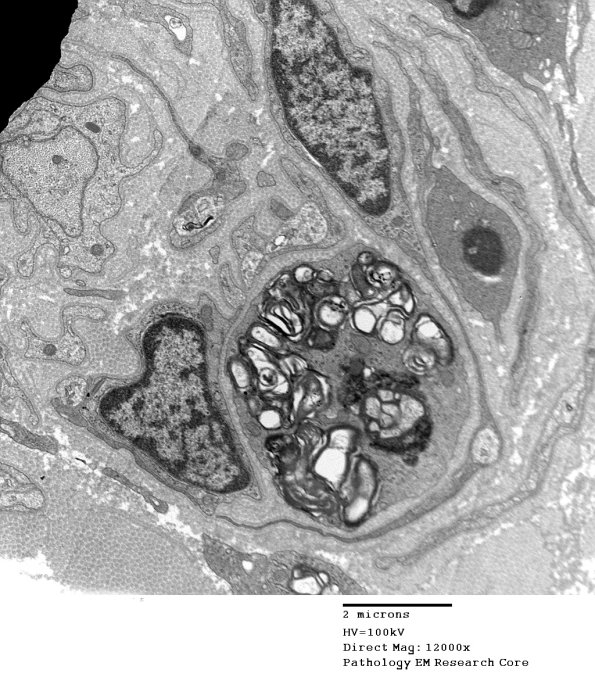

In this case a macrophage is leaving a demyelinated cell without onion-bulbs. (electron micrograph)